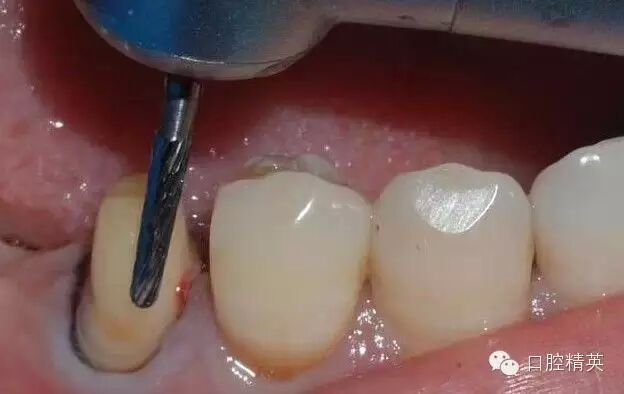

鄰面的制備,先用較細(xì)的金剛砂車(chē)針貼基牙鄰面制備,勿損傷鄰牙